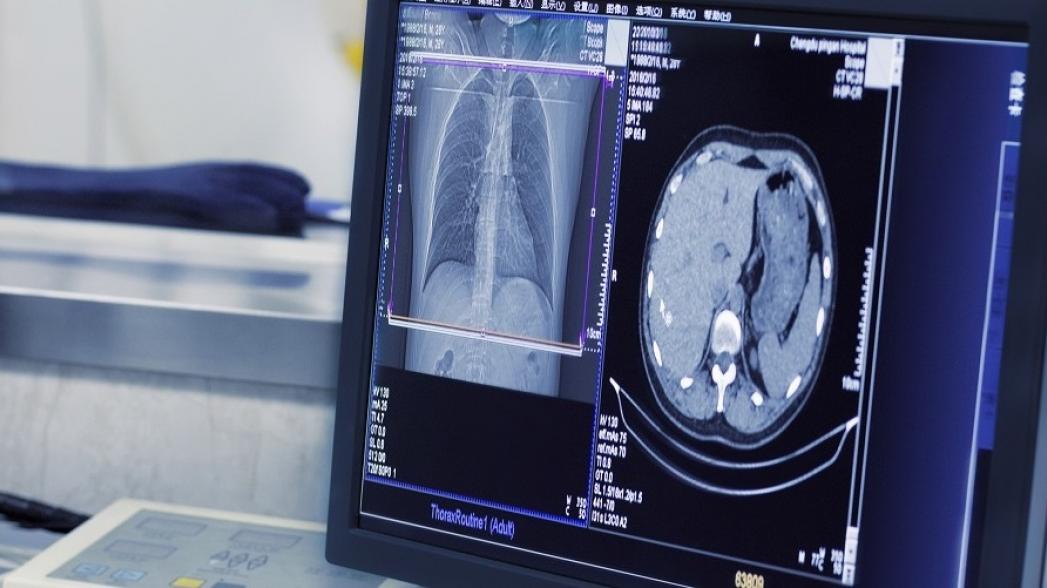

Категория: визуализация и диагностика.

Американская компания CureMetrix разработала алгоритм, используемый для анализа медицинских изображений, который в настоящее время тестируется для идентификации признаков рака легких по рентгеновским изображениям и рака груди в маммограммах. Используемая в решении технология отличается применением "умных выборок" данных, что позволяет отобрать из огромного массива больших данных релевантную информацию. Алгоритм машинного обучения исследует данные изображения, идентифицирует нужные атрибуты, исключая ненужную информацию и создает образцы, позволяющие точно продиагностировать пациента.

Стартап Enlitic, который специализируется на диагностике с использованием алгоритмов машинного обучения, работает совместно с австралийской сервисной компанией Capitol Health, чтобы вывести свое решение на рынок Австралии и Азии. Capitol Health одновременно является инвестором стартапа, вложив в него $10 млн. Решение Enlitic используется для анализа медицинских изображений с целью идентификации признаков рака легких и обнаружения переломов костей. Как говорится в пресс-релизе компании Enlitic, "впервые алгоритмы машинного обучения используются для автоматического обнаружения узелков рака легких на изображениях, полученных с помощью компьютерной томографии, с точность на 50% более высокой, чем это делают торокальные радиологи".